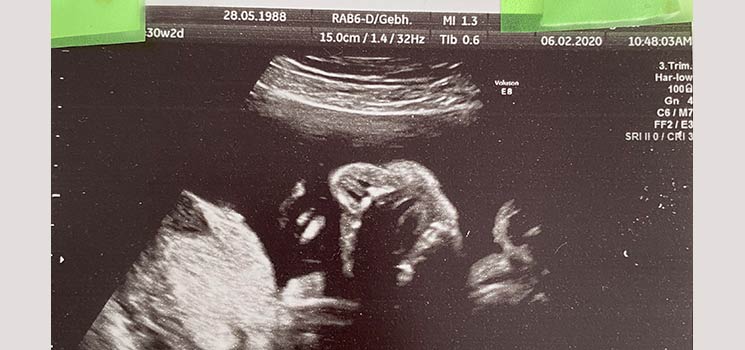

Stress, Luftnot, Wut & eine Überraschung - Tagebücher aus der Schwangerschaft von Pia aus Dortmund